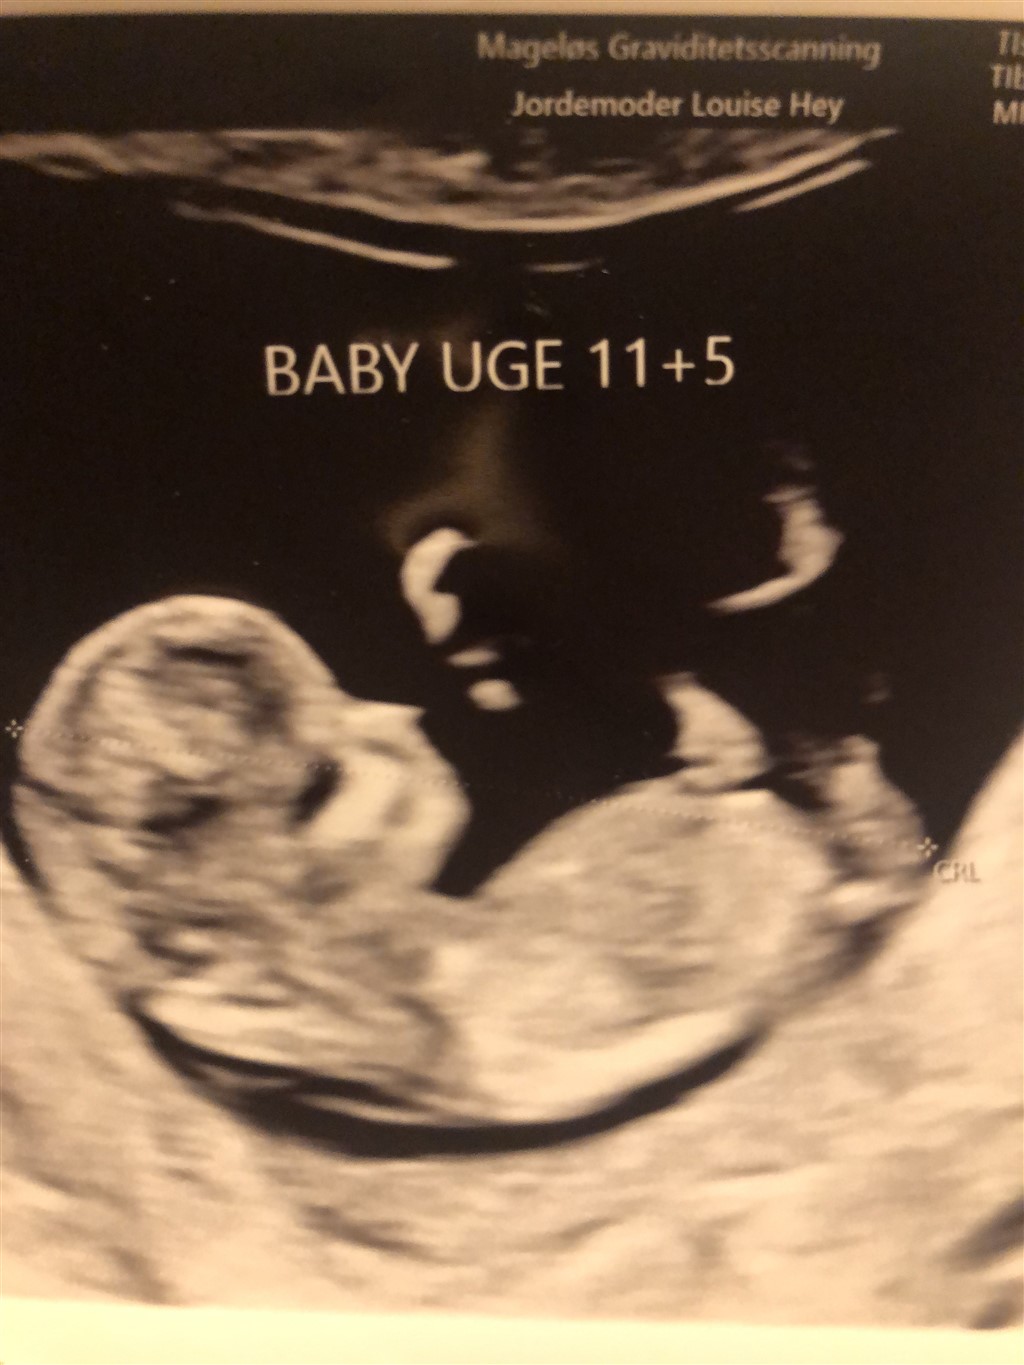

Jeg er overbevist om, at det er en dreng, men det er taget 11+5, så en anelse tidligt.

Tænker I det kan vise sig at være en pige?

Baby ligger en ikke helt lige, men er drejet. Det kan godt være, at det derfor er lidt sværere at få et retvisende billede